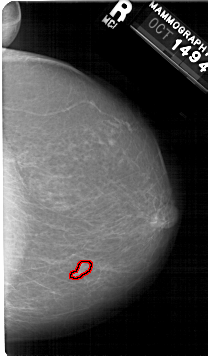

RIGHT_CC LINES 5326 PIXELS_PER_LINE 3106 BITS_PER_PIXEL 12 RESOLUTION 43.5 OVERLAY

FILE: A_1593_1.RIGHT_CC.OVERLAY

TOTAL_ABNORMALITIES 1

ABNORMALITY 1

LESION_TYPE MASS SHAPE FOCAL_ASYMMETRIC_DENSITY MARGINS ILL_DEFINED

ASSESSMENT 4

SUBTLETY 2

PATHOLOGY MALIGNANT

TOTAL_OUTLINES 1

BOUNDARY